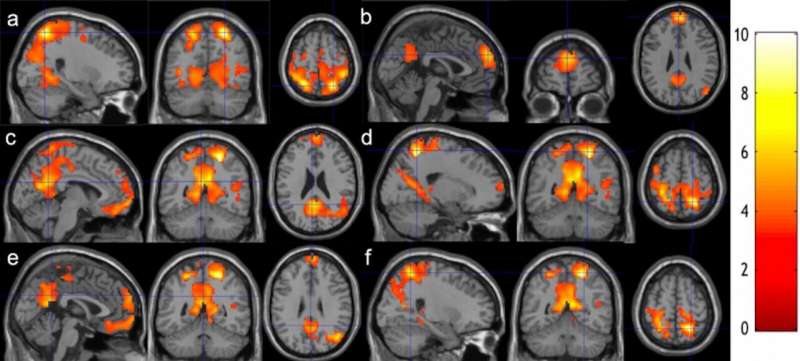

A new study from Binghamton University’s Thomas J. Watson College of Engineering and Applied Science tracked how practicing meditation for just a couple of months changed the brain patterns of 10 students in the University’s Scholars Program.

The findings of the study demonstrate that meditation can enhance the brain connection among and within these two brain networks, indicating the effect of meditation on fast switching between the mind wandering and focusing its attention as well as maintaining attention once in the attentive state.